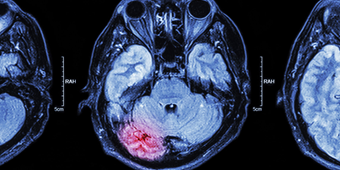

A loss of blood flow to the brain can cause slight or severe damage, depending on location and duration of the stroke.